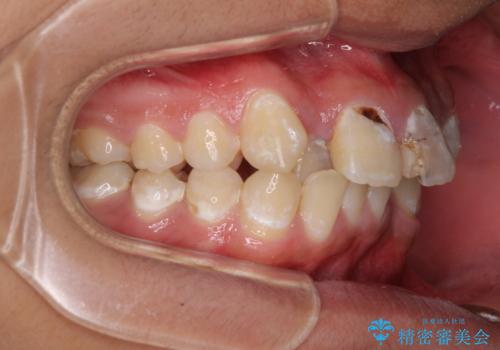

前歯のデコボコとむし歯だらけの歯列 矯正治療と虫歯治療

- 10代男性(高校生)

- むし歯が多く、歯並びも悪いとのことで、以前通院されていたご家族の紹介で来院された患者様です。

口腔内に無頓着であったため、まずはしっかりと歯磨きトレーニングを行い、必要な虫歯治療を行いました。

矯正治療は、むし歯が酷く抜歯が望ましい歯を1本抜歯して、ワイヤー装置にて整えることとしました。